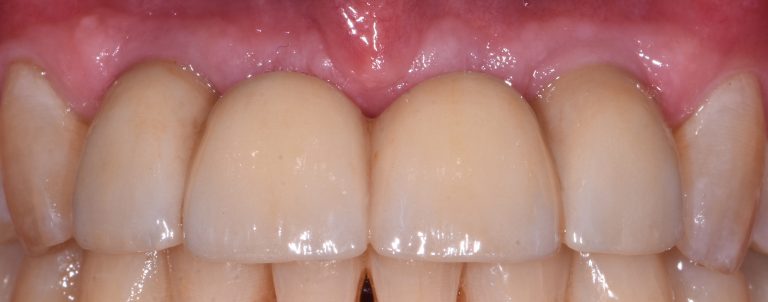

Implant Bridge (three to four Teeth)

- Implant bridge: Used to replace three to four missing teeth in a row.

Once the implant has been fully integrated with the bone, the next phase begins: the fabrication and placement of your permanent artificial tooth or teeth. This typically requires two to four appointments and combines the technical and artistic aspects of prosthodontics. Dr. Leong uses advanced technology and his expertise in dental aesthetics to create lifelike, durable restorations that blend seamlessly with your natural smile.

Once your final dental prosthetics are attached, you’ll be able to eat, speak, and smile confidently, just like you did with your original teeth.